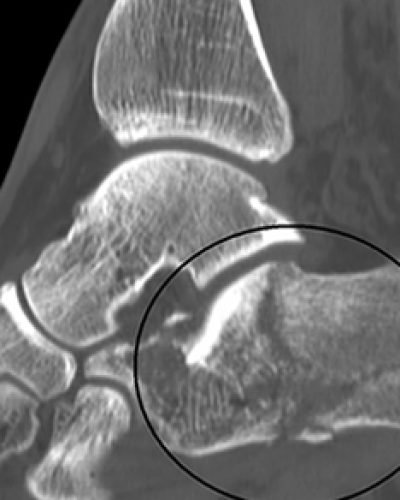

Physical Therapist’s Guide to Ankle Fracture An ankle fracture occurs when a bone on 1 or both sides of the ankle is partially or completely broken. Most ankle fractures are ... Continue reading ...